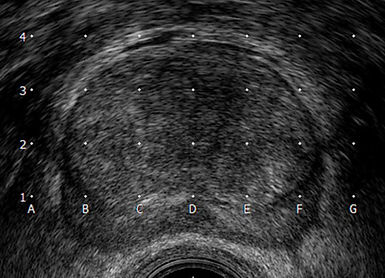

Į tiesiąją žarną įvedus ultragarso daviklį apžiūrima ir įvertinama prostata, atliekami ultragarso vaizdų ir kompiuterinės brachiterapijos planavimo sistemos kalibravimo darbai, užfiksuojami prostatos pjūviai kas 5mm, kurie reikalingi dozimetriniam planavimui.

Naudojant specialų skaičiais ir raidėmis sužymėtą tinklelį, gydytojas onkologas radioterpeutas ultragarso kontrolėje suduria adatas į suplanuotas prostatos vietas.